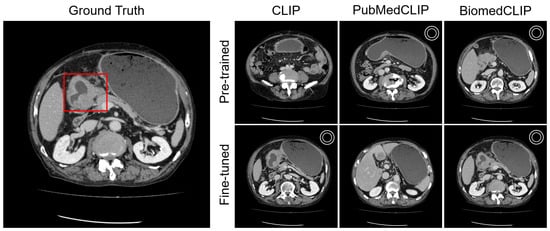

Appendix C.1. Lesion Awareness

Appendix C.2. Organ Awareness